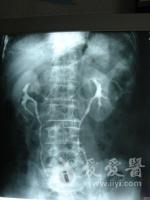

静脉尿路造影1

静脉尿路造影2

静脉尿路造影3